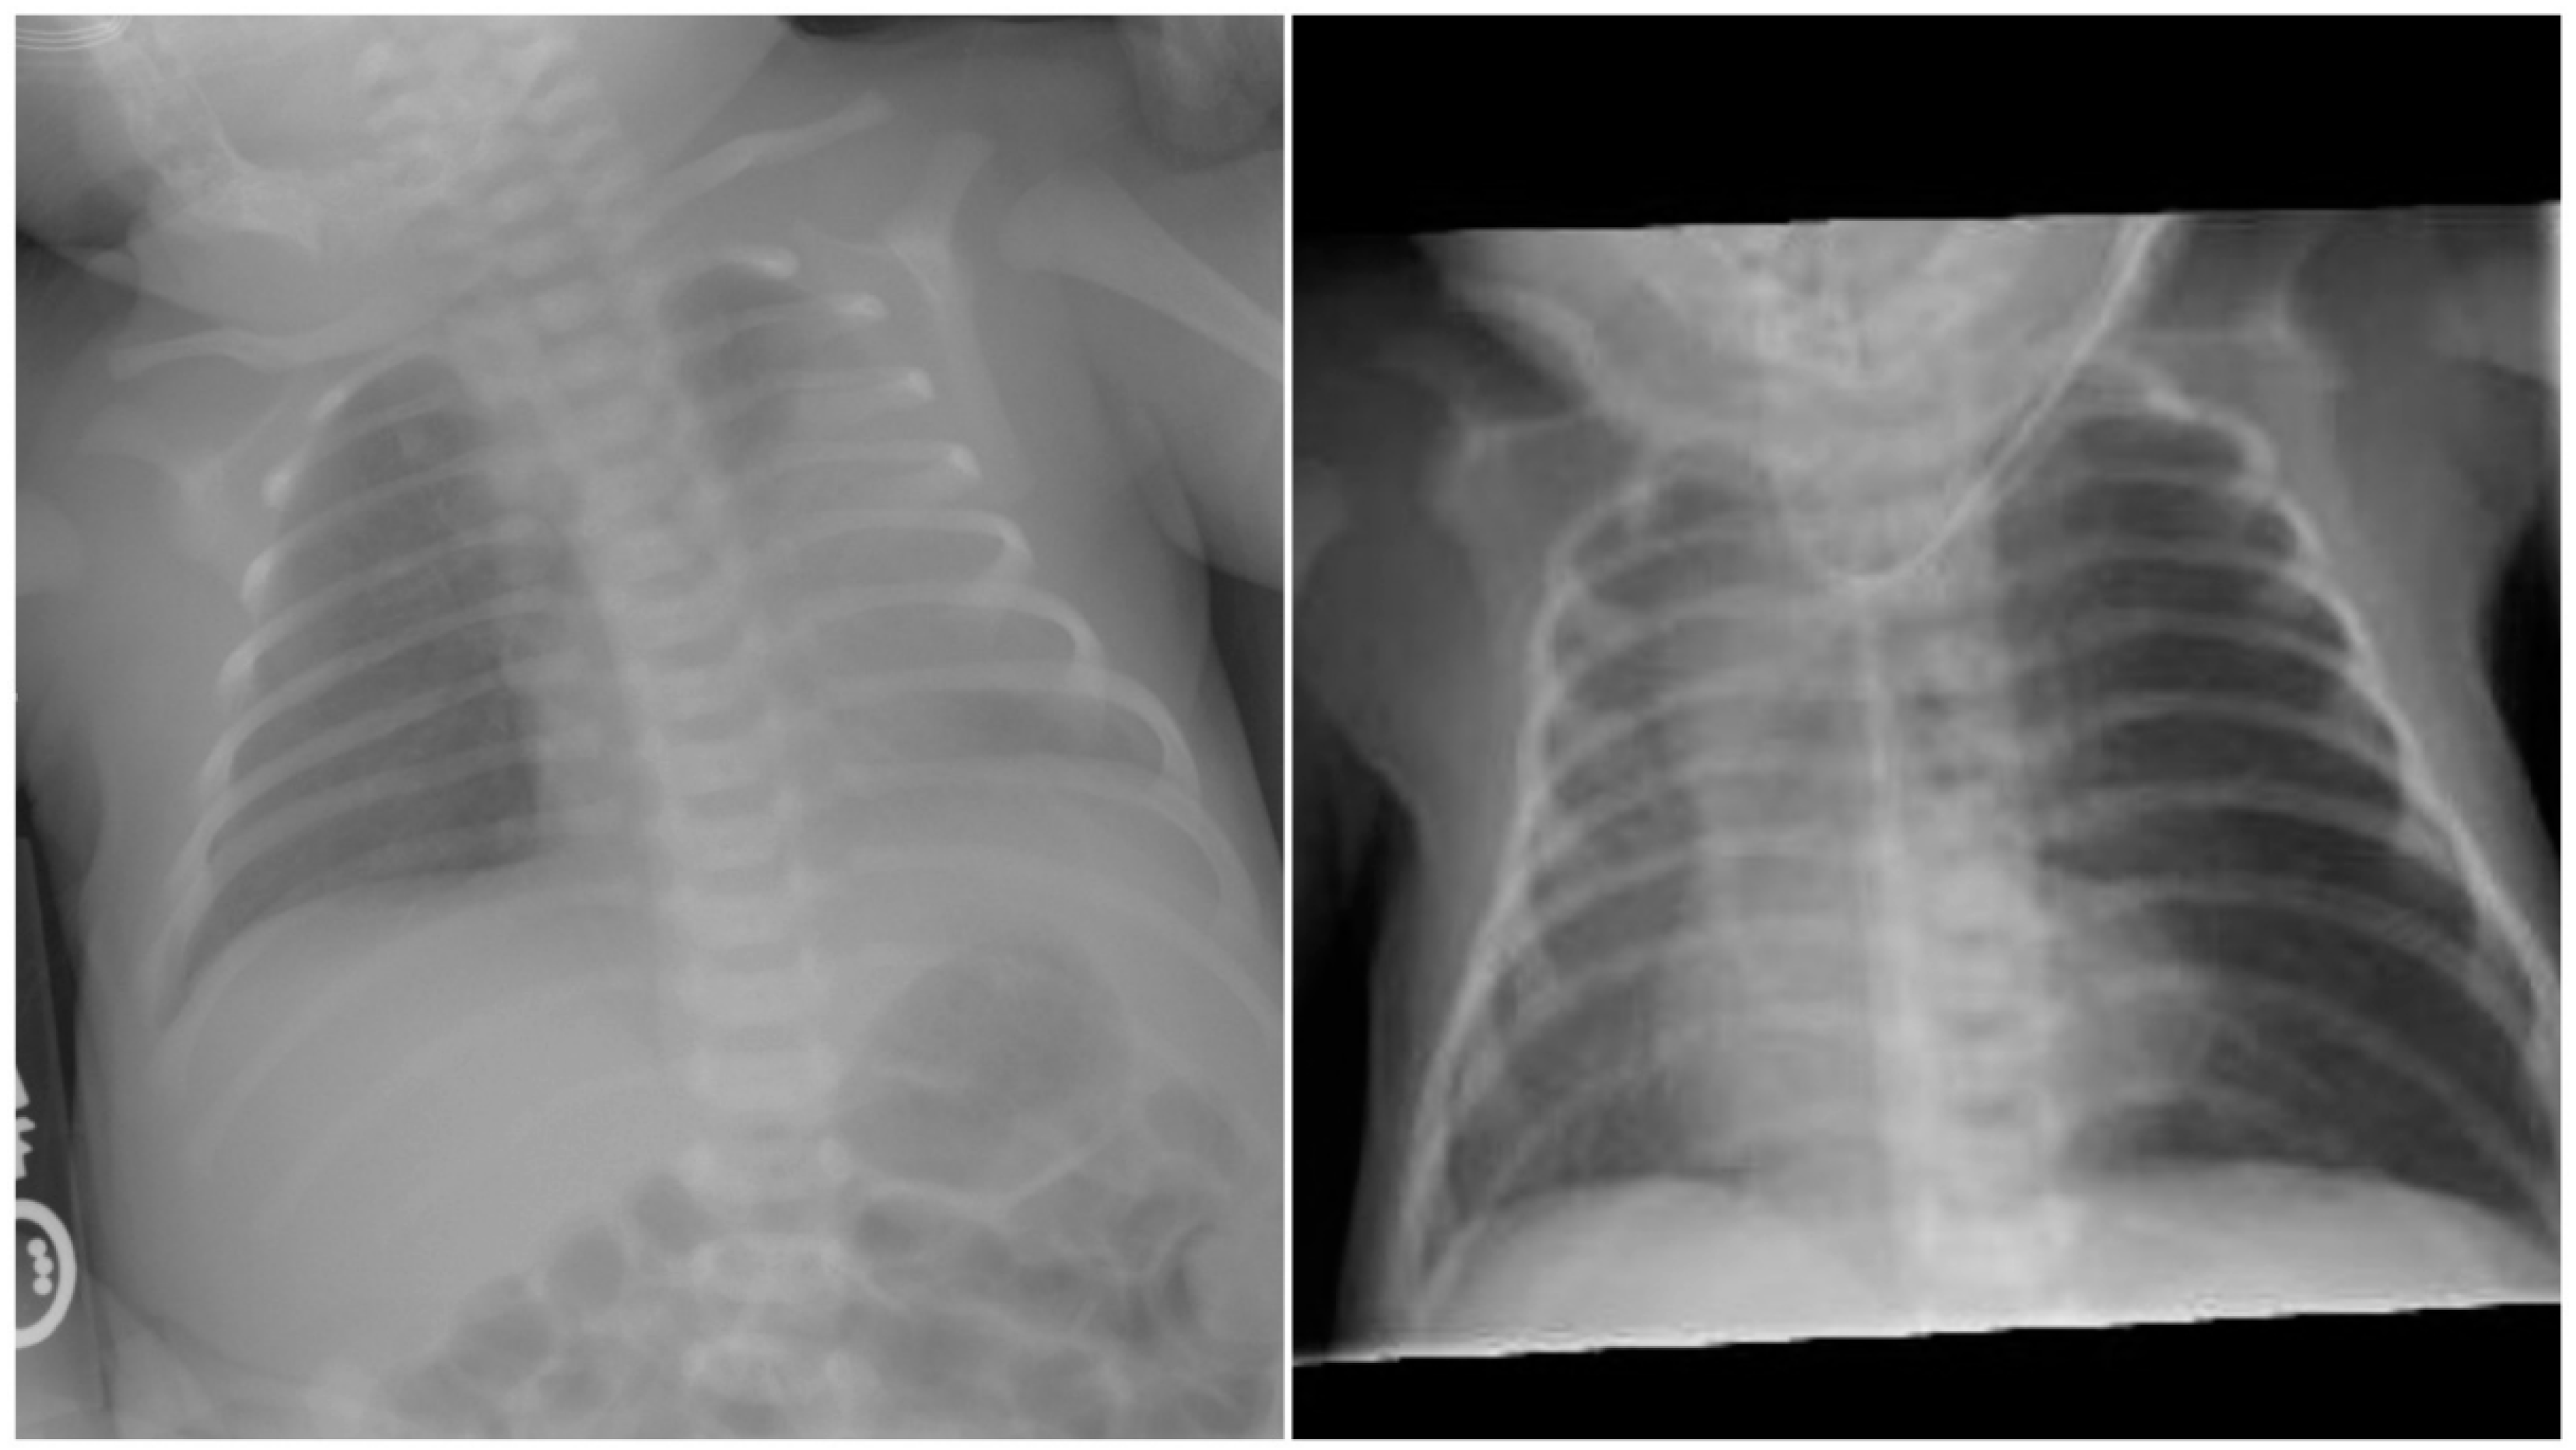

Figure 1.

Left panel depicts anterio-posterior chest radiograph on the first day with left-sided opacification. Right panel reveals radiograph at 7 days with hyperinflation of the left and mediastinal shift.